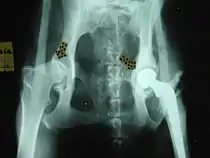

- النمو الشاذ للورك:

- استئصال عظم رأس الفخذ

- القَطْعُ الثلاثي للعَظْمِ الحَوضِيّ

- استبدال مفصل الورك